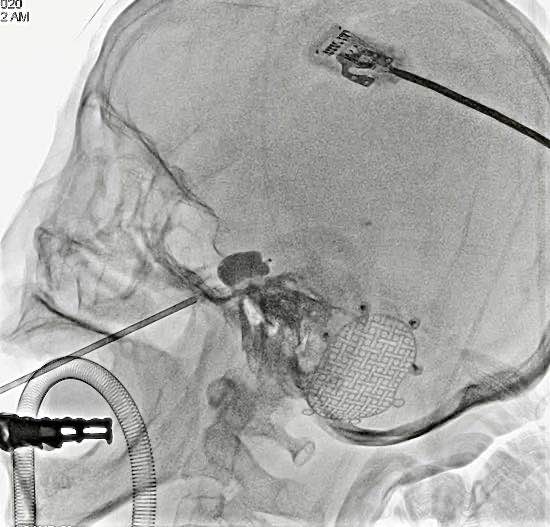

8月14日袁阿姨被推进导管室,术中3D重建后选择最优投照角度,在双C正侧位透视下,3D导引板引导穿刺针顺利植入卵圆孔内,进而置入球囊,充盈压迫3分钟后撤出,整个手术操作时长10分钟。术后袁阿姨颜面部疼痛即刻完全缓解,而创口仅仅是面部口角旁的一个小针眼,3天后袁阿姨顺利出院。